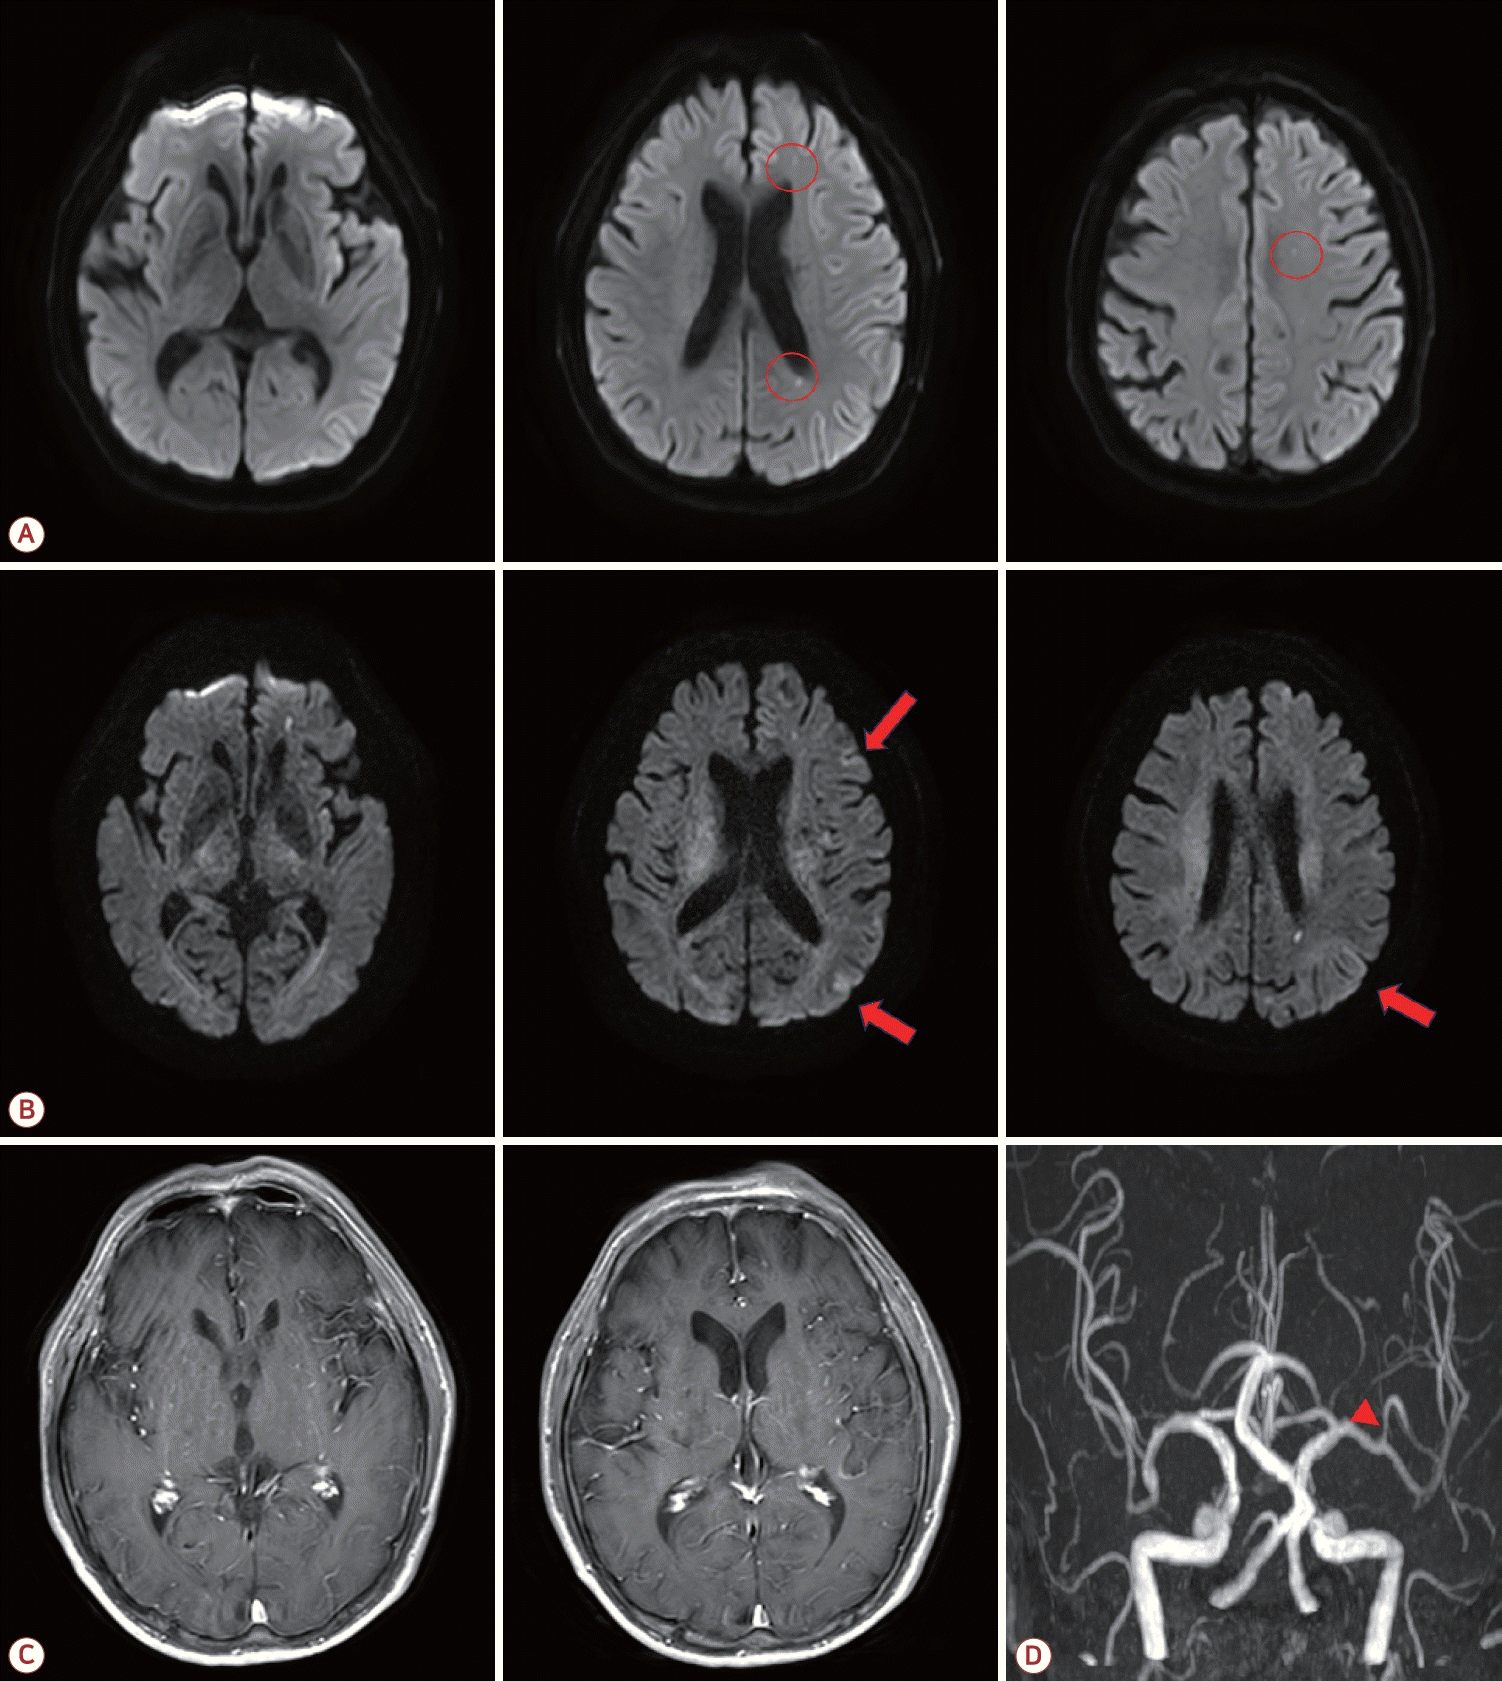

70세 남자가 초기 발열로 지역 응급 의료 센터에 방문하여 진료 중 추가 발열이나 경련 없이 실어증과 우측 근력 저하가 나타났다. 자기공명영상(magnetic resonance imaging, MRI) 확산강조영상에서 좌측 대뇌동맥 영역에 다발성 고신호강도의 병변이 확인되어 초급성 뇌경색의 치료를 위하여 본원 응급실로 증상 발생 4시간 만에 전원되었다(Fig. A).

증상 발생 4시간 40분에 추가로 진행된 확산강조영상에서 처음 확인된 뇌병변 이외에 대뇌 피질을 따라 고신호 병변이 추가로 확인되었다(Fig. B). T1 조영증강영상에서 뚜렷한 연수막 조영증강은 확인되지 않았다(Fig. C). 한달 전 뇌수막염으로 입원하여 진행한 뇌혈관영상과 비교하여 경미한 좌측 중대뇌동맥 위분지에 동맥경화가 악화 없이 확인되었다(Fig. D).

Brain magnetic resonance imaging of the patient. (A) Initial diffusion-weighted imaging (DWI) revealed multiple small diffusion restrictions in the left cerebral hemisphere (red circles). (B) Follow-up DWI obtained after 3 hours revealed additional lesions and suspected high signal intensity in the left cerebral cortex (red arrows). (C) T1 gadolinium-enhanced imaging showed no prominent meningeal enhancement. (D) Magnetic resonance angiography revealed stenosis in the superior division of the left middle cerebral artery (red arrowhead).